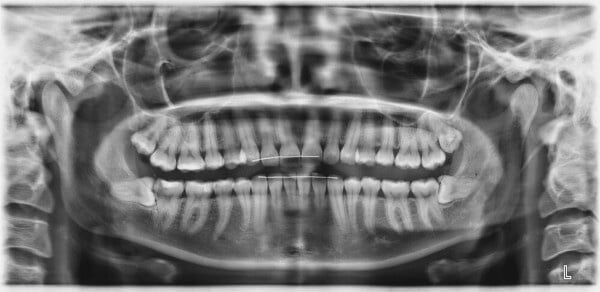

Die jeweils letzten Backenzähne (Molaren) am Ende der Zahnreihen von Ober- und Unterkiefer werden Weisheitszähne genannt. Man nennt sie so, weil sie meist erst zwischen dem 16. und 25. Lebensjahr aus Kieferknochen und Weichgewebe durchbrechen. Häufig kommen bei einem Erwachsenen vier Weisheitszähne vor, doch können es auch weniger sein. Manchmal finden die Weisheitszähne nur teilweise oder gar nicht an die Oberfläche, was zu verschiedenen Problemen führen kann.

Normalweise verfügt ein Mensch über insgesamt 32 Zähne. Dazu gehören bei den meisten Menschen vier Weisheitszähne – je einer in jedem Gebissquadranten. Es gibt aber auch Menschen, die weniger oder gar keine Weisheitszähne entwickeln. Die Gründe sind ein komplexes Zusammenspiel aus individuellen genetischen und evolutionären Faktoren, die letztlich darüber entscheiden, wie viele Weisheitszähne ausgebildet werden.

Bei der Weisheitszahnentfernung ist eine gründliche Voruntersuchung von entscheidender Bedeutung. Durch eine umfassende Voruntersuchung und die Verwendung eines dreidimensionalen DVT-Röntgenbildes kann der Zahnarzt oder Oralchirurg die genaue Lage der Weisheitszähne präzise bestimmen und den Eingriff planen. Dies minimiert das Risiko einer Verletzung des sensiblen Unterkiefernervs und verringert die Gefahr einer vorübergehenden Taubheit der Unterlippe. Während des Eingriffs erfolgt in den meisten Fällen ein Schleimhautschnitt, gefolgt von der Freilegung der Zahnkrone, der möglichen Teilung des Zahns und der Entnahme der einzelnen Zahnteile. Abschließend wird die Wunde mit Nähten verschlossen.